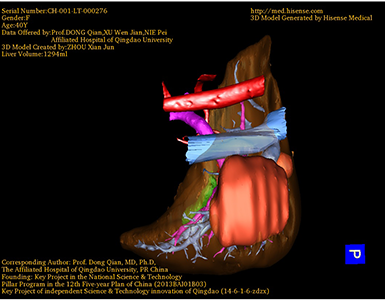

术前三维重建:重建图片

通过调节窗宽窗位调整CT序号,对肿瘤,肝实质,胆囊,下腔静脉,肿瘤,肝动脉、门静脉及肝静脉等进行三维重建;系统自动计算肿瘤体积和肝脏体积。

模拟手术操作,自动计算切除肿瘤体积。肝脏体积为1294ml,肿瘤体积为158.5ml,肿瘤体积为肝脏体积的12.2%,通过比对40-50岁正常肝脏体积为1368.38±279.24 ml,通过术前模拟手术,精准判断切除后剩余肝脏体积能耐受,避免肝衰竭发生。

术前手术方案的规划。